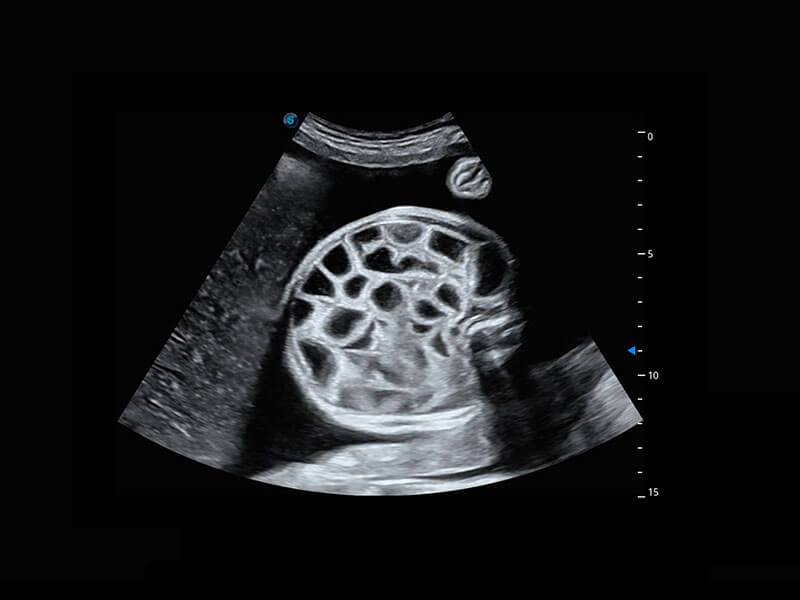

高分辨率容积成像-早孕胎儿

胎儿体循环

光影成像-孕囊